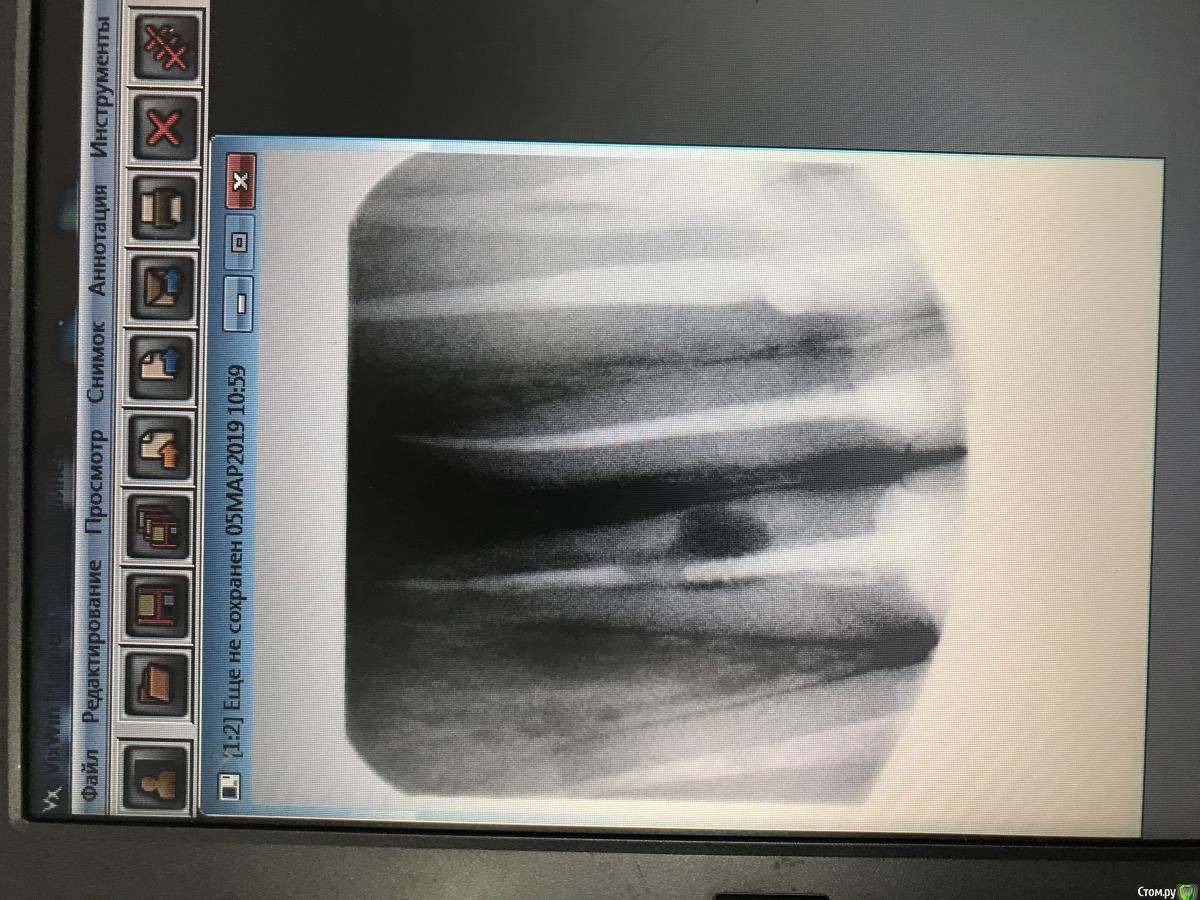

dr.Dre Опубликовано 5 марта, 2019 Поделиться Опубликовано 5 марта, 2019 Добрый день Коллеги .Пациентка 27 лет ,жалобы боль при накусывании,свищ с небной стороны,зуб покрыт безметаловой коронкой.Как бы поступили в данной ситуации? Ссылка на комментарий

___49___ Опубликовано 5 марта, 2019 Поделиться Опубликовано 5 марта, 2019 Прицельного мало , нужен еще анамнез - давно ли носит коронку , когда появились боли, был ли предварительно хруст , подвижность, вставьте гуту в свищ и сделайте повторный снимок , а лучше КТ. Было на памяти несколько зубов с перфой от штифта которые приходилось резецировать и закрывать ретроградно ....но в вашем случае штифт откровенно короткий . Ссылка на комментарий